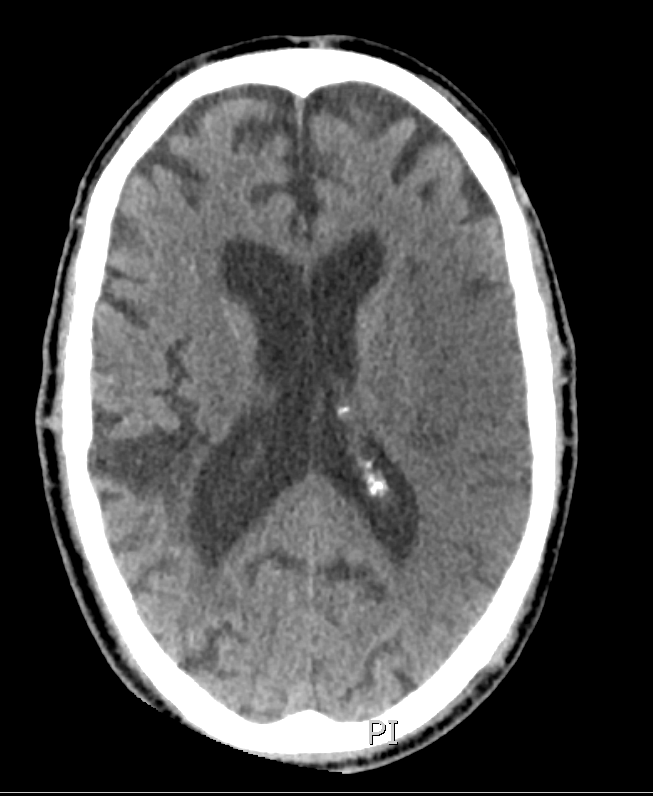

One of the first steps of acute stroke management is to obtain a non-enhanced head CT. A previously healthy patient is now having symptoms of an ischemic stroke. What is the earliest typically time after symptom onset that would you generally expect to see evidence of an ischemic stroke on non-enhanced head CT?

The answer is C) 6 hours – as a rule of thumb, this is usually the earliest time frame in which you might see evidence of an ischemic stroke on CT. For most patients, presenting with the 4.5 hour tPA time window, we expect to see a normal head CT.

Injured and dying brain tissue no longer has ATP to run the cell membrane Na+/K+ pump, causing the cells to swell with water – it is this increase in water in the dying cell that causes early hypodensity on CT.

The key point here is that most hyper-acute ischemic strokes do NOT show up on head CT! It takes time to develop. The key role of a head CT in acute stroke is to rule out intracranial hemorrhage and identify other conditions that would contraindicate tPA.